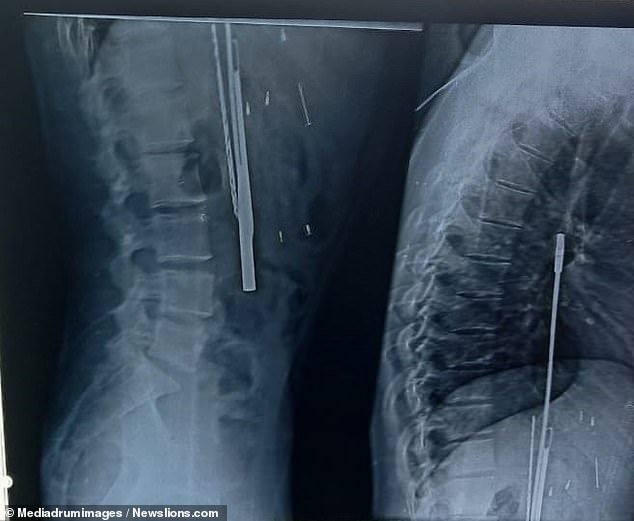

كشف موقع "ميرور" البريطاني عن قيام أطباء باستخراج 33 قطعة"خردة" من معدة شاب، بما في ذلك أدوات حلاقة وسكاكين ومفك براغ، بعد أن اشتكى من ألم شديد في بطنه.

وذكرت التقارير الواردة أن يوغيش

ثاكور

، عانى أيضا من وجود مواد بلاستيكية في بطنه، بعد نقله إلى المستشفى لإجراء فحص الأشعة السينية.

وكان على السيد ثاكور إجراء عملية جراحية بعد اكتشاف الأجسام الحادة في معدته، وسيتلقى أيضا مساعدة نفسية، وفقا للتقارير.

ويعتقد الأطباء أن الرجل قد يعاني من "فساد الشهية"، وهو اضطراب في الأكل يتسبب في استهلاك المصابين لأشياء حادة، حسبما ذكرت صحيفة "ديلي ميل".

وقال الأطباء أيضا إن ثاكور عانى من تغير في الحالة العقلية: تغيرات عامة في وظائف المخ، أو عيوب في التفكير.

وبحسب ما ورد، قال الجراح الذي أجرى العملية إنه صدم لدى عثوره على كل هذه "الخردة" في أحشاء الرجل المصاب.